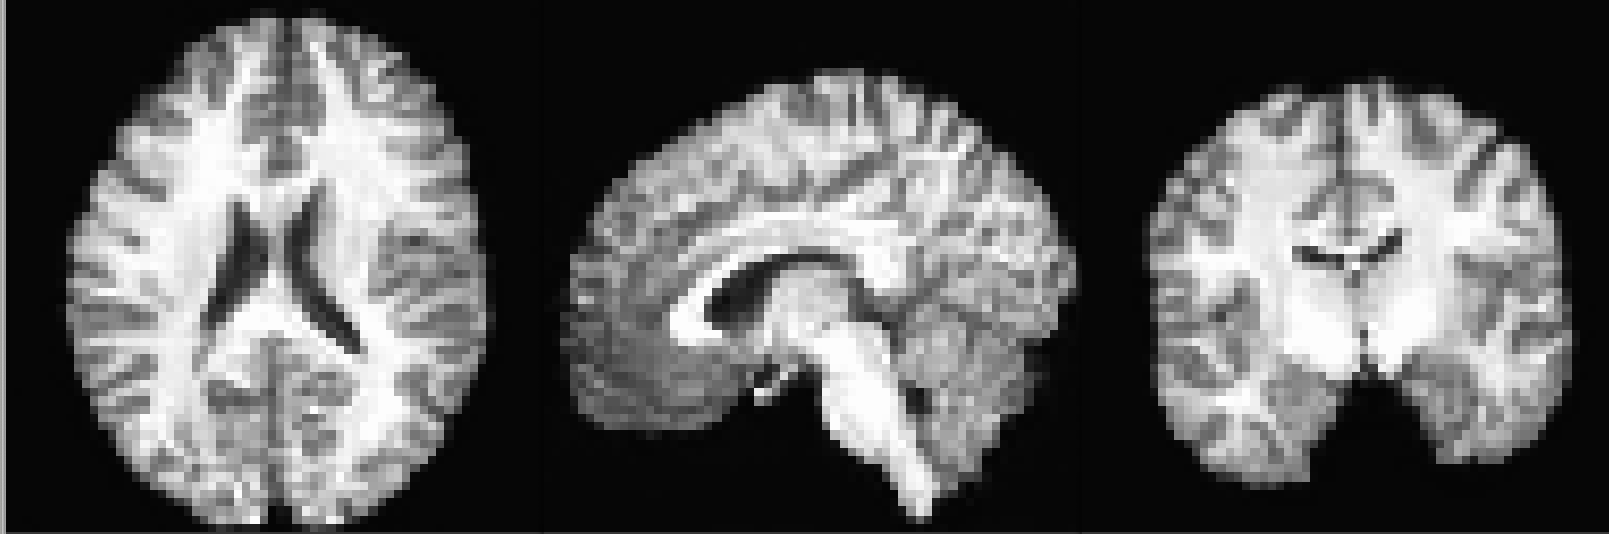

Figure 1 shows some synthetic brains with a resolution of 32 x 32 x 32 voxels generated by our 3D PGAN, while Figure 2 shows some synthetic brains with a resolution of 64 x 64 x 64 voxels.

We have demonstrated that a 3D progressive growing GAN can be used to synthesize T1-weighted volumes of 64 x 64 x 64 voxels. The synthetic volumes can be used for training (convolutional) networks that perform classification or segmentation. Furthermore, synthetic volumes can be shared freely, as they do not belong to a specific person, and can therefore facilitate data sharing [23]. In future work we will synthesize volumes of higher resolution.